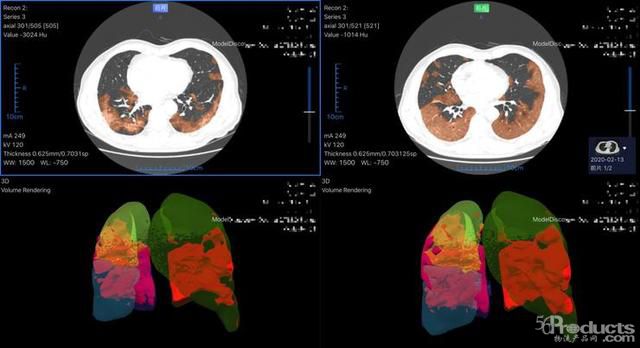

以最早進(jìn)入武漢一線的數(shù)坤新冠肺炎人工智能影像輔助診斷系統(tǒng)為例,面對(duì)300-500層胸部圖像,系統(tǒng)可在2-3秒內(nèi)自動(dòng)完成肺部感染區(qū)域體積、密度、分期等多個(gè)臨床指標(biāo)的計(jì)算,為危重患者的搶救贏得寶貴時(shí)間。

數(shù)坤AI在武漢一線醫(yī)院使用

數(shù)坤AI及時(shí)對(duì)病情進(jìn)行評(píng)估